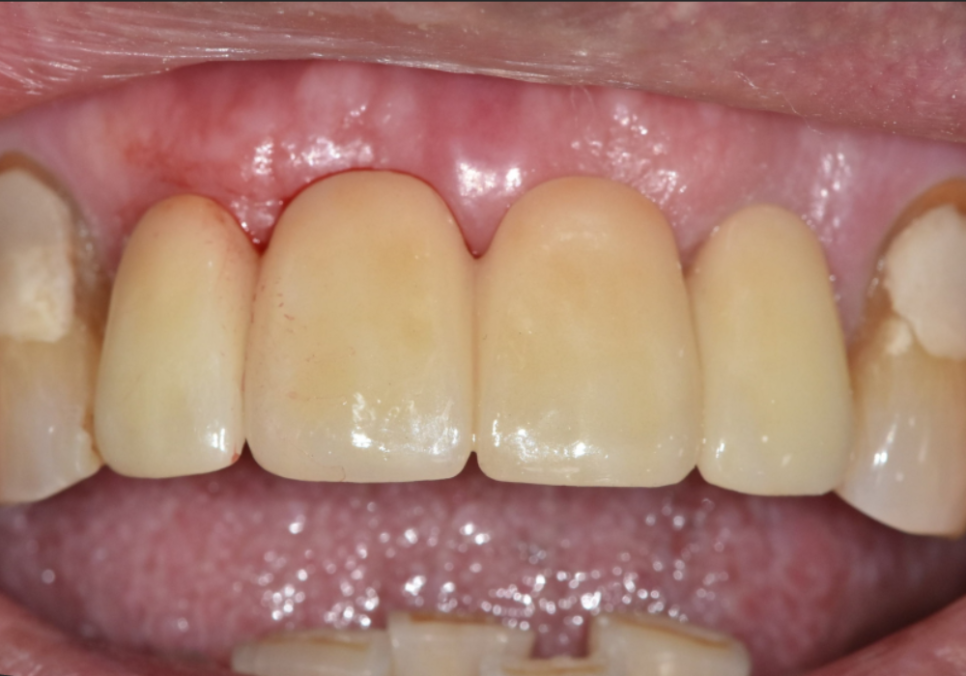

이 환자분은

왼쪽 앞니가 충치로 인해 부러지면서

내원하셨습니다.

250221

겉으로 보면

앞니 하나만 문제가 있어 보일 수 있지만,

입안을 자세히 살펴보니

앞니 4개 모두 흔들림이 있었고

잇몸뼈 높이도 많이 낮아져

있는 상태였습니다.